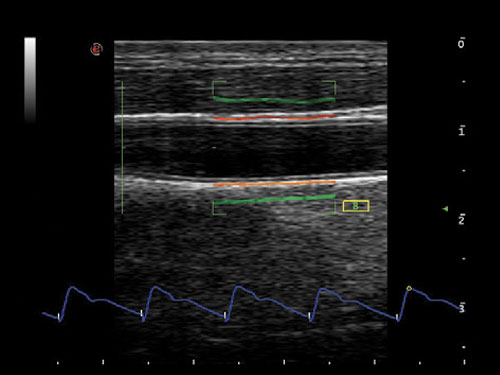

QIMT: Automatická detekce tloušťky média Intima v reálném čase, včetně směrodatné odchylky a indexu spolehlivosti, na základě analýzy RF signálu.

QAS: RF datová technologie umožňuje automaticky a přesně měřit tuhost karotické stěny a automaticky vypočítat indexy PWV, CC, AI, α, β.